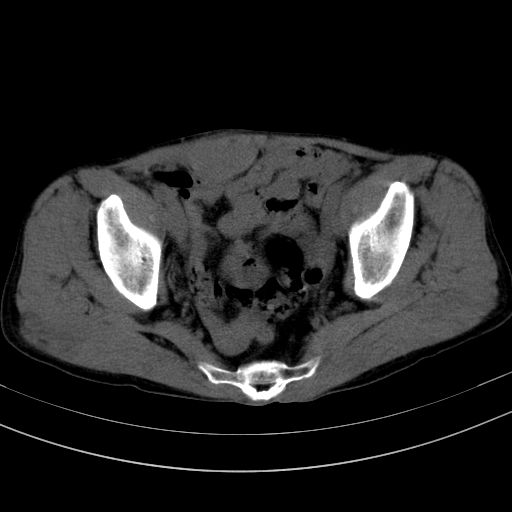

以下是引用37度在2010-1-9 14:37:00的发言:[br]1.双肾囊肿,左肾积水结石,.胆总管轻度扩张;[br]2.病灶在腹膜外,考虑纤维瘤。

以下是引用dyqct在2010-1-9 17:56:00的发言:[br]考虑:1.双肾囊肿,左肾积水结石、旋转不良。[br] 2.右侧腹直肌血肿或纤维瘤。[br]肠道准备不好。做个增强。